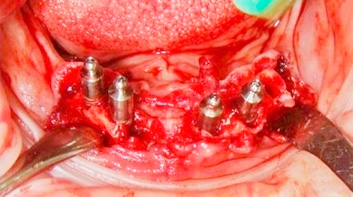

Клинический случай 1. Имплантация методом немедленной нагрузки с установкой протеза

1) Панорамная рентгенограмма больной 57 лет, по показаниям удаление зубов нижней челюсти.

2) Удаление зубов нижней челюсти.